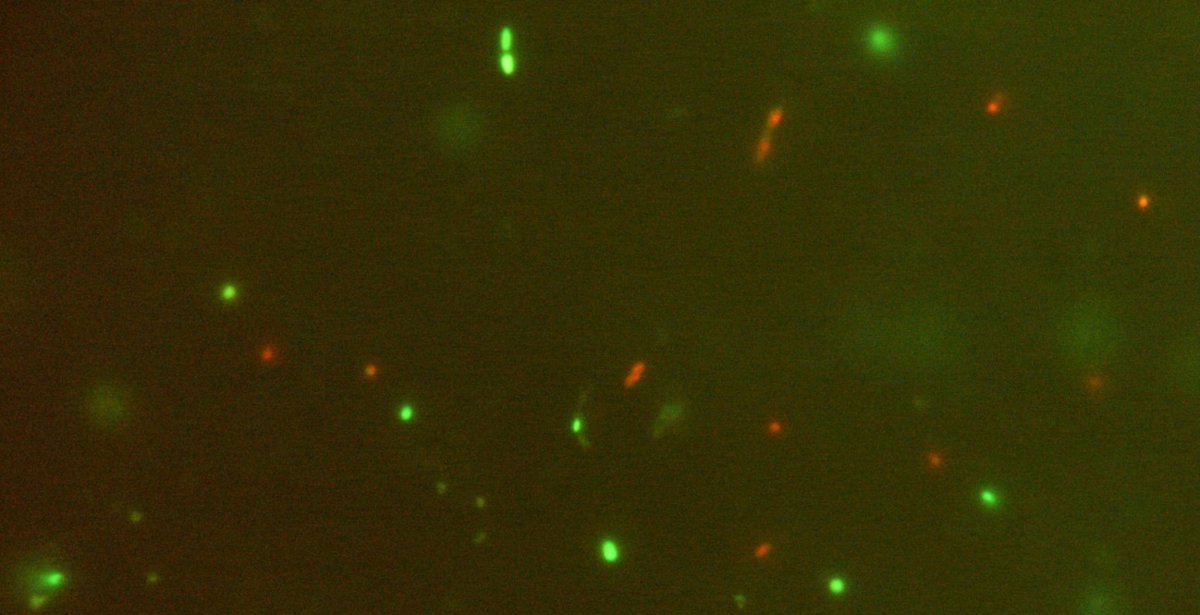

Un estudio en el participan el Consejo Superior de Investigaciones Científicas (CSIC) y la Universidad de Oviedo ha demostrado que enriqueciendo con bacterias beneficiosas la microbiota de individuos con lupus se consigue que se parezca más a la de individuos sanos, un descubrimiento que podría abrir la puerta a modificar la respuesta de las células inmunes a través de una manipulación terapéutica de la microbiota.

El trabajo, que se ha publicado en la revista 'Scientific Reports', ha partido de estudios previos en los que ya habían demostrado las 'diferencias significativas' entre poblaciones microbianas en las heces de personas sanas e individuos con lupus, que se manifestaban por un descenso de la ratio Firmicutes/Bacteroidetes. A través de un método que permite separar la microbiota intestinal del resto de contenido fecal, han añadido bacterias de cepas de 'Bifidobacterium bifidum', 'Ruminococcus obeum' y 'Blautia coccoides'.

"Hemos comprobado que cuando estas bacterias se ponen en contacto con las células inmunes se corrige parcialmente el desequilibrio inmunológico que padecen las personas lúpicas", ha señalado el investigador del CSIC Abelardo Margolles, del Instituto de Productos Lácteos de Asturias.